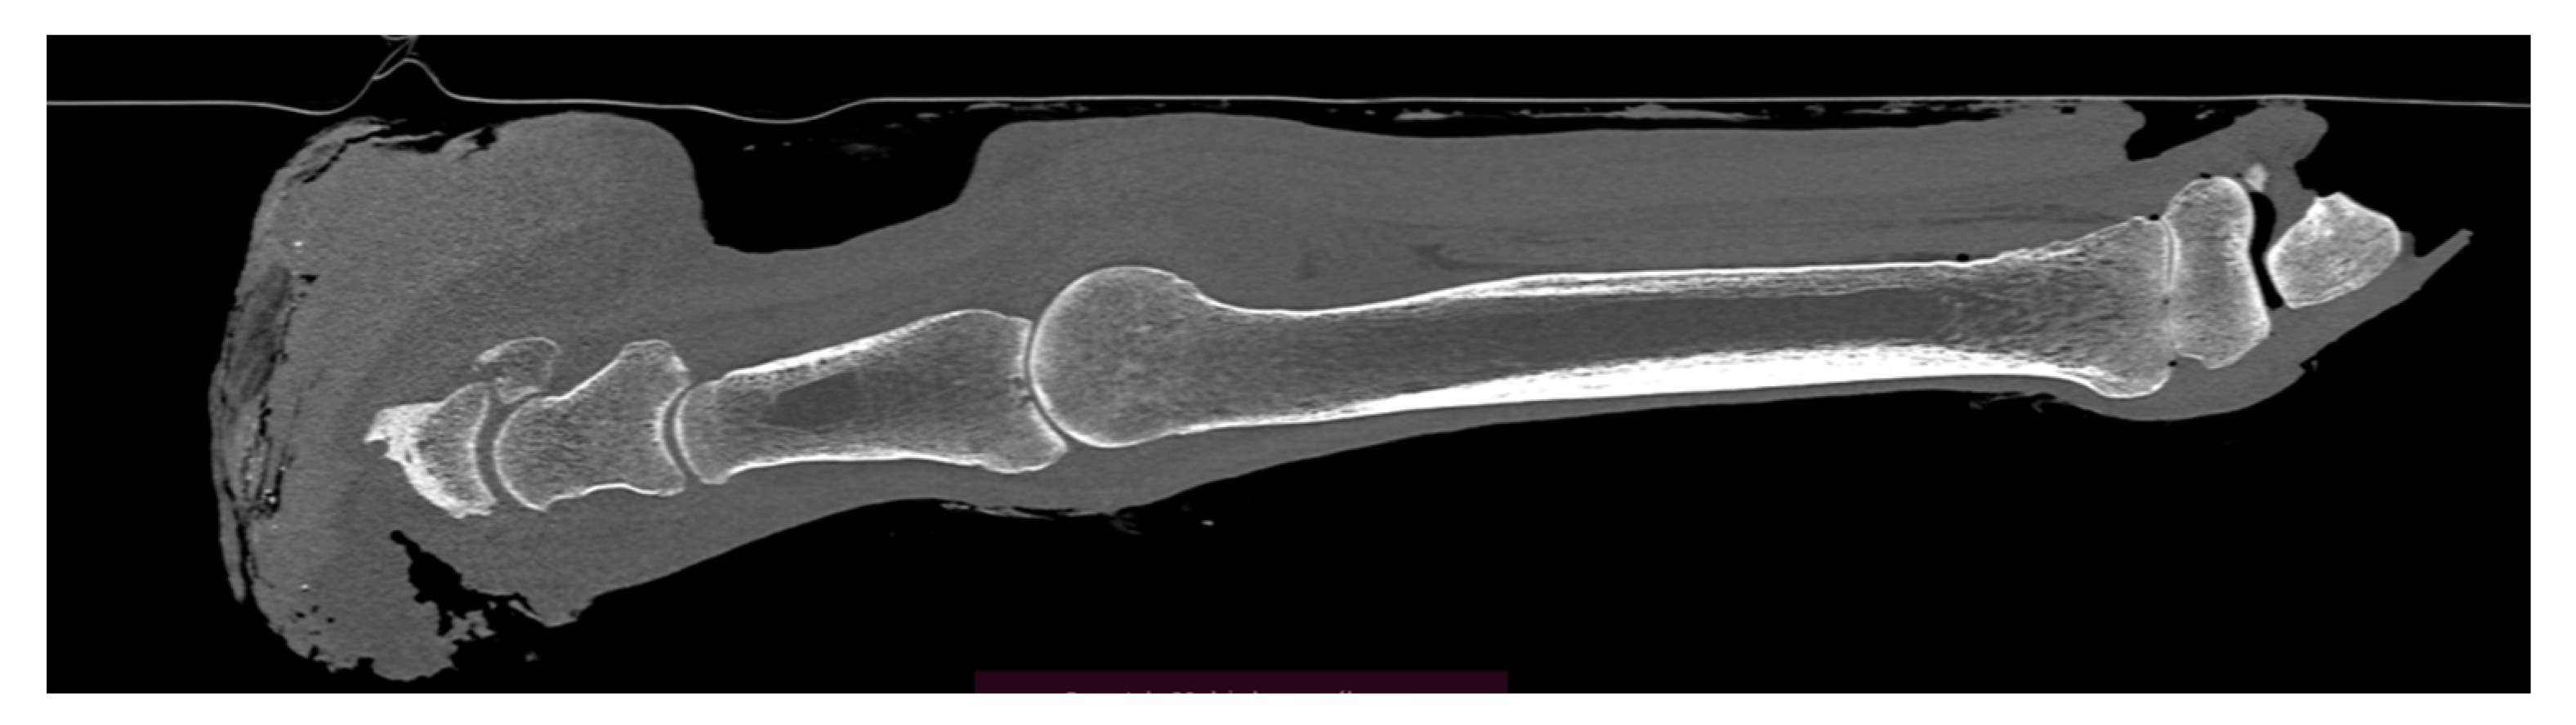

Case Presentation